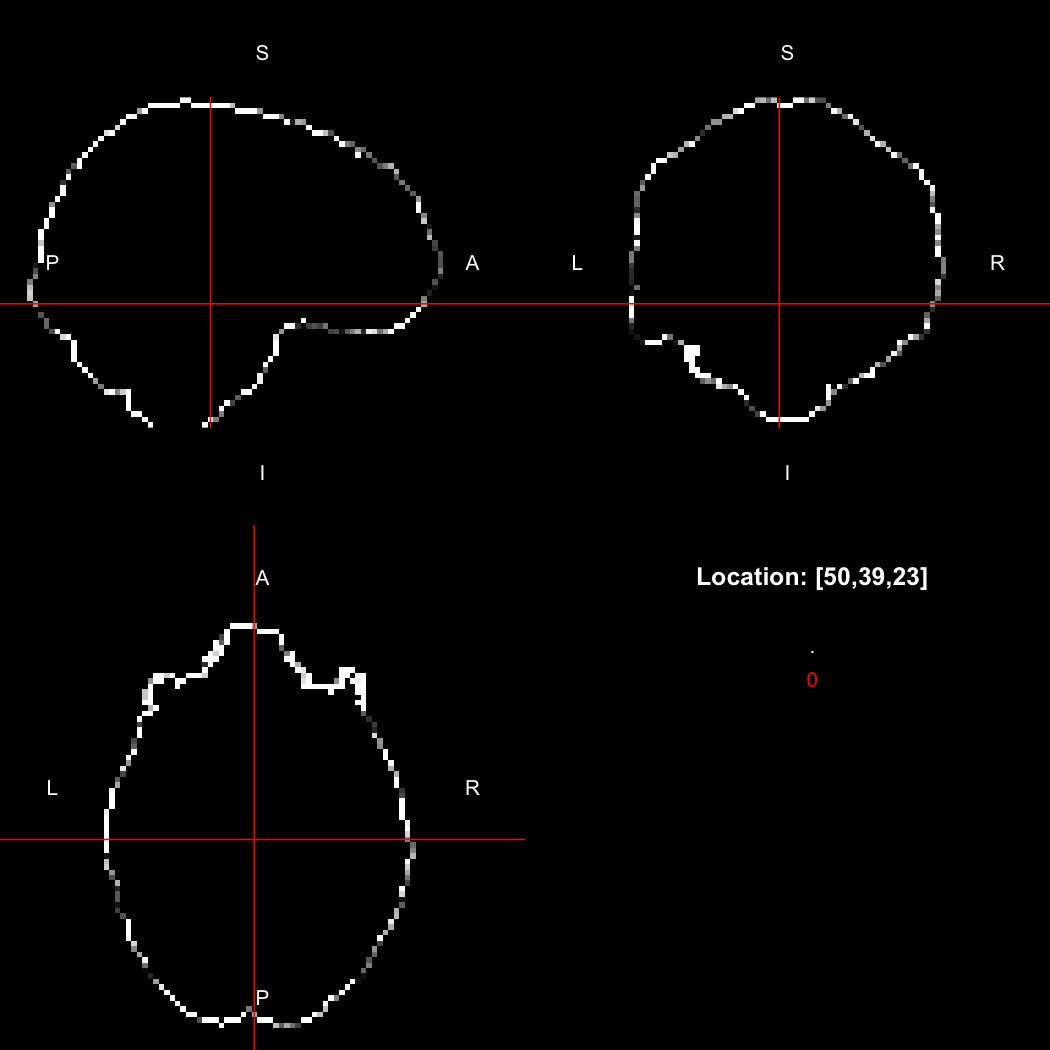

image %>% kernel_sphere(radius=3) %>% dilate() %>% subtract(image) %>% view()

## Setting window to (0, 60)

This example sets up a spherical kernel of radius 3 mm, dilates the image with it, and then subtracts the original image from the result to leave just the outer edge of the imaged object.